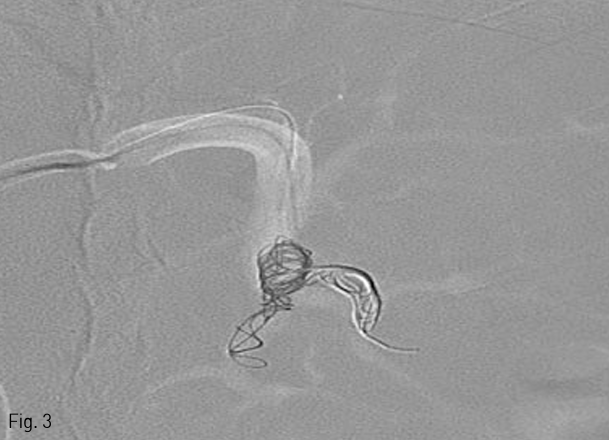

5 Fr Yashiro catheter (Terumo, Tokyo, Japan)를 복강동맥을 통해 비장동맥에 삽입한 후 혈관조영술을 시행하여 비장동맥의 분지들을 먼저 확인하였다 (Fig. 2). 0.021 inch guide wire (GT guide wire; Terumo)와 2.7 Fr microcatheter (Progreat; Terumo, Tokyo, Japan)를 이용하여 co-axial technique으로 middle segmental artery가 분지된 이후 splenic hilum에서의 비장동맥에 12mm×3cm 1개, 10mm×3cm 3개의 platinum coils (IDC: Interlocking Detachable Coil; Boston Scientific, Tokyo, Japan)와 gelfoam (Cutanplast, Mascia Brunelli Spa, Milano, Italy), N-butyl cyanoacrylate (NBCA; Histoacryl; B.Braun, Melsungen, Germany)와 Lipiodol (Guerbet, Paris, France) 1:4 혼합물을 이용하여 superior, inferior segmental artery를 색전하였다 (Fig. 3). 색전 후 비장동맥 조영술에서 splenic hilum level에서 원위부 색전이 이루어진 것을 확인하였다(Fig. 4).

Fig 2

Angiogram for splenic artery shows superior, middle, and inferior segmental branches.